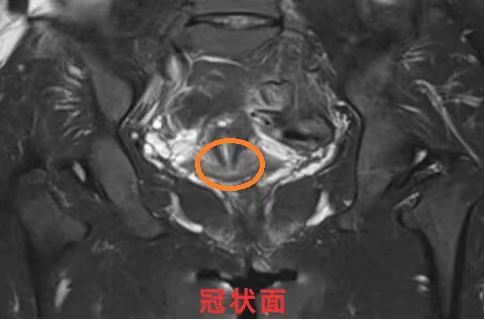

以上3张图(矢状面、冠状面、横断面)中圈出位置可见MRI:子宫后壁近宫颈处见结节状短T1信号。